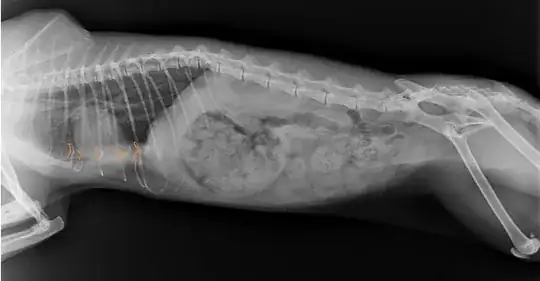

Beside that, we went to a vet to check this cat, blood test, temp., x-ray... so after taking x-ray we saw that her ribs have a strange shape. Local vet says that it seems that this cat suffered possible impact in that area, but he is not sure.

My question is; is it possible that x-ray is mistaken, because of a sudden movement?

Also second x-ray in different cat position shows different shape of ribs.

Can anyone explain, how can I interpret it?